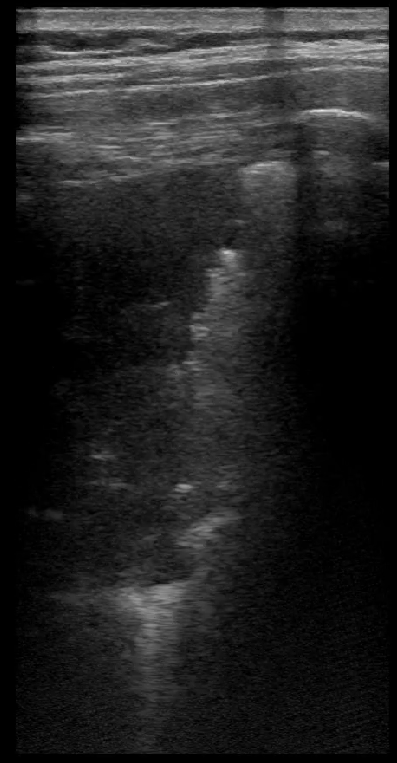

Realizamos una ecografía clínica en la que vemos líneas A en todos los campos pulmonares izquierdos. Sin embargo, en los derechos, observamos abundantes líneas B, especialmente en campos medios y una imagen de consolidación del parénquima pulmonar.

En nuestro caso, la ecografía fue fundamental para acelerar el diagnóstico y administrar la medicación de manera rápida, pues en la misma consulta en la que se exploró a la paciente, se completó el estudio ecográfico. Asimismo, la ecografía permitió descartar complicaciones asociadas como el derrame pleural y permitió comprobar que la vesícula o los riñones, presentaban características anodinas. Es posible que de haber contado con un ecógrafo en el PAC en el que fue atendida, se podría haber diagnosticado y tratado con anterioridad a la paciente.